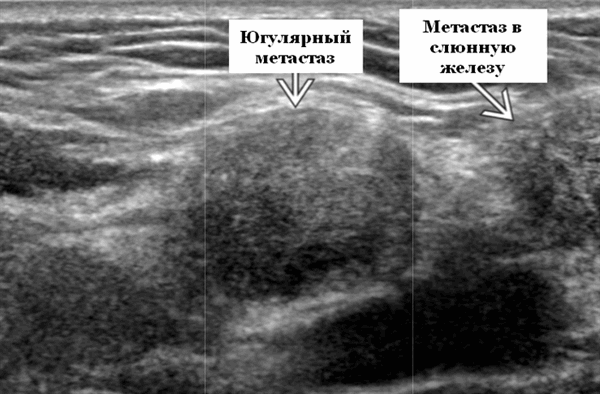

Метастатическое поражение околоушных узлов на УЗИ

Ключевые факты. Терминология. Лимфатическая или гематогенная опухоль распространяется на внутрижелезистые околоушные лимфатические узлы. Нормальная околоушная железа имеет внутрижелезистые лимфатические узлы, которые определяются на УЗИ (в отличие от подчелюстных и подъязычных желез). Околоушные и перипаротидные узлы: уровень 1-го порядка при плоскоклеточном раке кожи и меланоме волосистой части головы, ушной раковины и лица.

Данные ультразвукового исследования слюнных желез

- Одиночные или множественные гипоэхогенные образования при известном распределении внутрипаротидных лимфоузлов.

- На ультразвуковом сканировании образование четко или плохо определено (экстранодальное распространение)

- Необходимо искать локальную инвазию: интрапаротидную, в наружную сонную артерию, ретромандибулярную вену, экстрапаротидные мягкие ткани.

- На УЗИ определяется аномальная внутренняя архитектура ± эхогенные ворота, эхогенность однородная или неоднородная с внутренними кистозными участками в некротических узлах

- ± Метастатические шейные лимфатические узлы

- Интранодулярный кровоток хаотичный / дезорганизованный или преимущественно периферический

- Ультразвуковое сканирование дает оптимальную характеристику лимфоузлов в поверхностной доле и проведение подтверждающей биопсии.

Визуализация. Общие особенности. Само по себе ультразвуковое сканирование метастазов в околоушные лимфоузлы неспецифична. Одиночные или множественные околоушные образования. Хорошо выраженный или плохо выраженный лимфоузел (экстранодальное распространение), однородный или неоднородный с внутренним некрозом. На УЗИ с ЦДК внутриузловая васкуляризация или усиление кровотока. Патология связана с известным первичным раком, часто в прилегающей коже или региональной области головы и шеи. Околоушные и перипаротидные узлы: узловая станция 1-го порядка при плоскоклеточной карциноме кожи (ПКК) и меланоме латеральной части волосистой части головы, ушной раковины / наружного слухового прохода и передней части лица